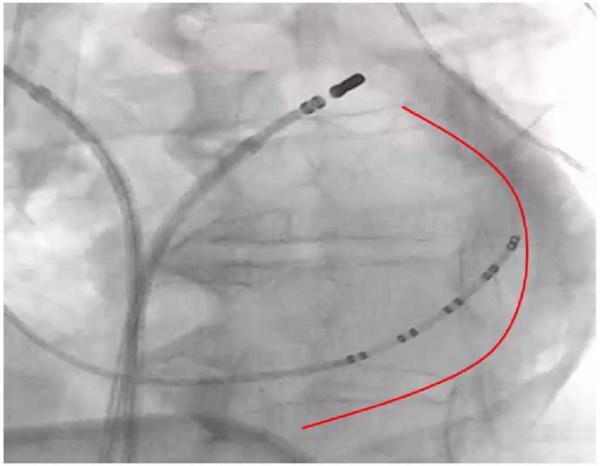

Рис. 3. Пациент 43 лет.

Примечание: в течение года после проведенной РЧА ипсилатеральных ЛВ описывает кашель, одышку, а также многократное возникновение пневмонии, требовавшей проведения антибактериальной терапии. A — данные КТ, стрелкой показаны пораженные сосуды: окклюзия верхнедолевого ствола ЛВ, стеноз среднедолевого ствола ЛВ (50%) справа. И этапы интервенционного лечения: B — контрастирование сосудов и сердца до проведения ангиопластики; C — ангиопластика верхнедолевого ствола правой ЛВ; D — конечный результат операции после проведенного стентирования ЛВ.

Сокращения: КТ — компьютерная томография, ЛВ — легочные вены, РЧА — радиочастотная катетерная аблация.